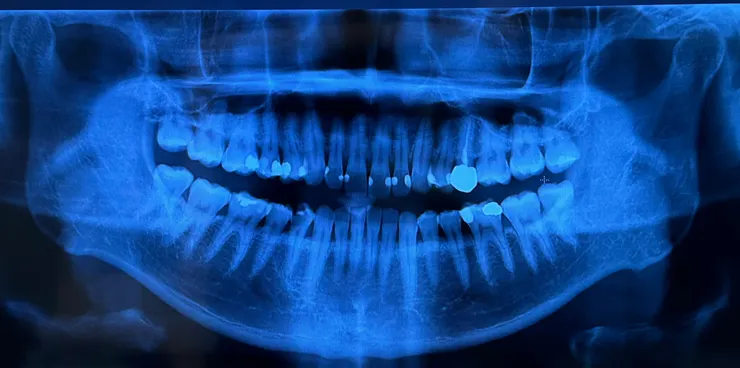

案例二